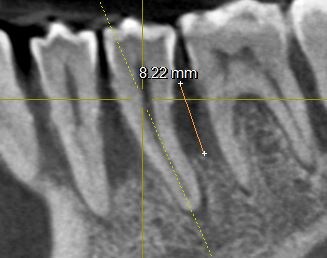

Пародонтит – это инфекционное заболевание тканей, окружающих зуб. При неудовлетворительной домашней и нерегулярной профессиональной гигиене, а также при поздней диагностике стоматологом пародонтита, зубной камень и налет нарушают соединение десны с зубом. Они проникают все глубже и глубже, вследствие чего происходит разрушение костной ткани (см фото). При тяжелой стадии пародонтита – зубы теряют опору, становятся подвижными. Что в свою очередь ведет к их потере..

убыль кости